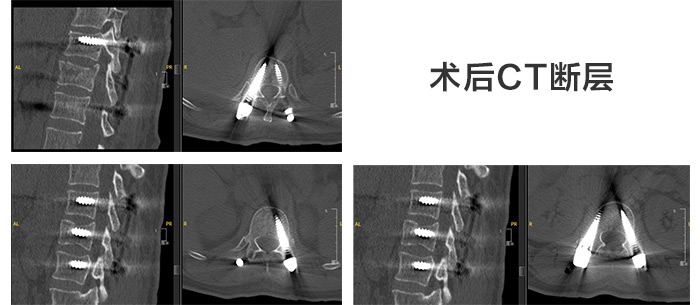

第二天,尚军主任、孟磊医生手术团队在“天玑”骨科机器人定位下,通过3D图像扫描规划手术中椎弓根螺钉的进钉点、置钉方向以及置钉深度。根据机器人系统导航,通过机械臂定位,切开约2cm切口进行精准置钉,保障神经安全和手术的有效性,所有操作一步到位。最后C型臂透视检查骨折复位,脊柱生理序列恢复满意,内固定物位置良好。